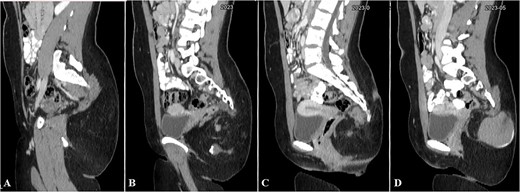

Contrast-enhanced computed tomography (CT) showed an ill-defined mass-like lesion in the gluteal region. The lesion consists of mixed tissue (fat predominantly, fluid and calcifications) and is seen exerting mass effect on the adjacent muscles and extending into the ischioanal, ischiorectal fossa and pre-coccygeal region (Figs 1 and 2).

Selected axial CT cuts of the pelvis with oral and IV contrast (Arterial phase) from above downward (A–D), showing the mentioned gluteal mass measuring about 9 × 15 × 0.5 cm3. The boundaries of the lesion were not clearly defined and the dimensions were assumed based on its mass effect on the adjacent structures. The lesion consisted of mixed tissues (fat predominantly, fluid and calcifications). The fluid portion appeared on the right aspect of the gluteal region with high density, indicating mucinous/proteinaceous content. Extensions into the ischio-rectal fossa are noted with minimal pre-coccygeal components seen as well.